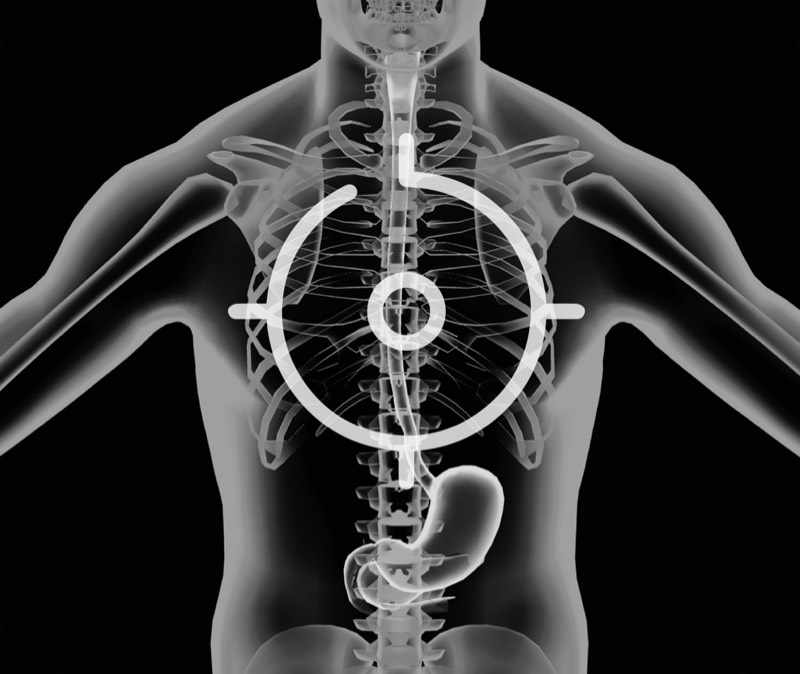

超声电子上消化道内窥镜

360°电子环形扫查与高清内镜影像相结合,提供了良好的插入性能和高清的内镜图像

卓越的宽频设计,满足医生探查不同深度的组织和器官